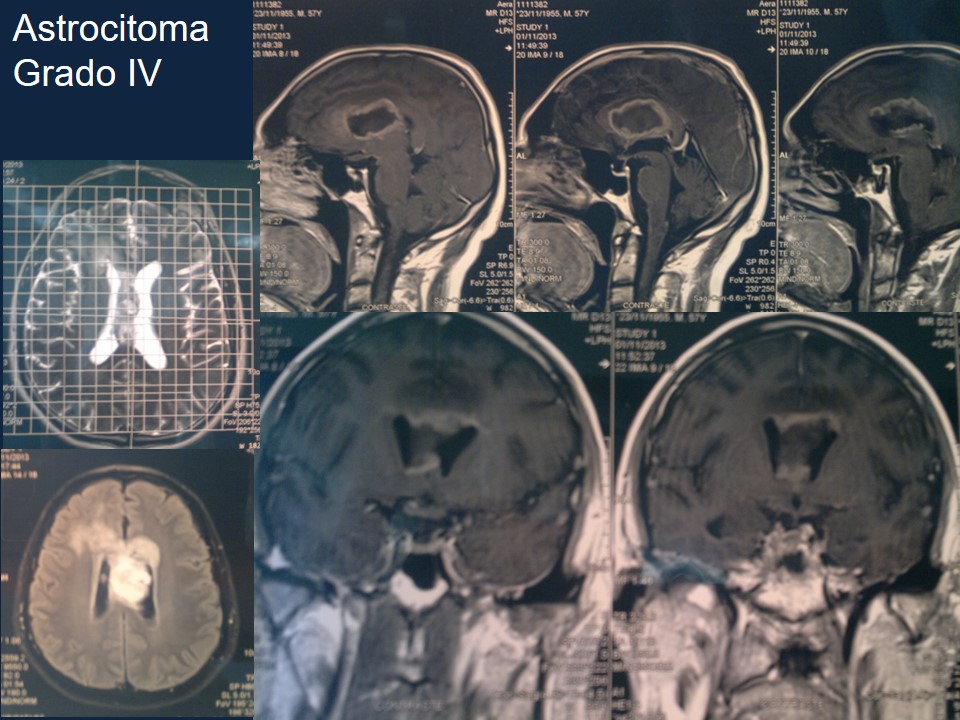

Metodología Estereotáctica o Estereotaxia